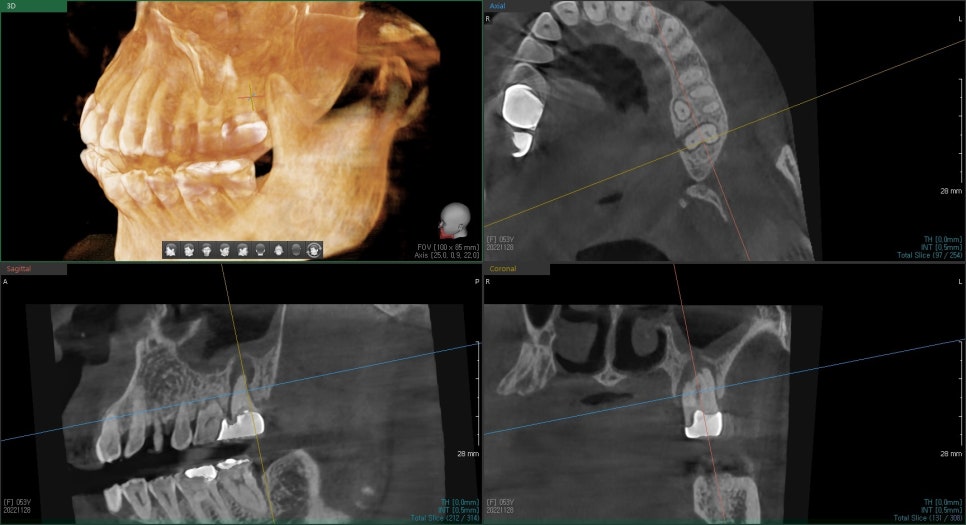

발치 전 CT를 찍어 주변 치조골을 평가했습니다.

치아 뿌리 주변이 염증으로 흡수가 되어있어서

발치 후 바로 임플란트 수술이 불가하고

발치 공간에 치조골 이식을 통해 뼈를 형성하고 수술을 진행기로 했습니다.